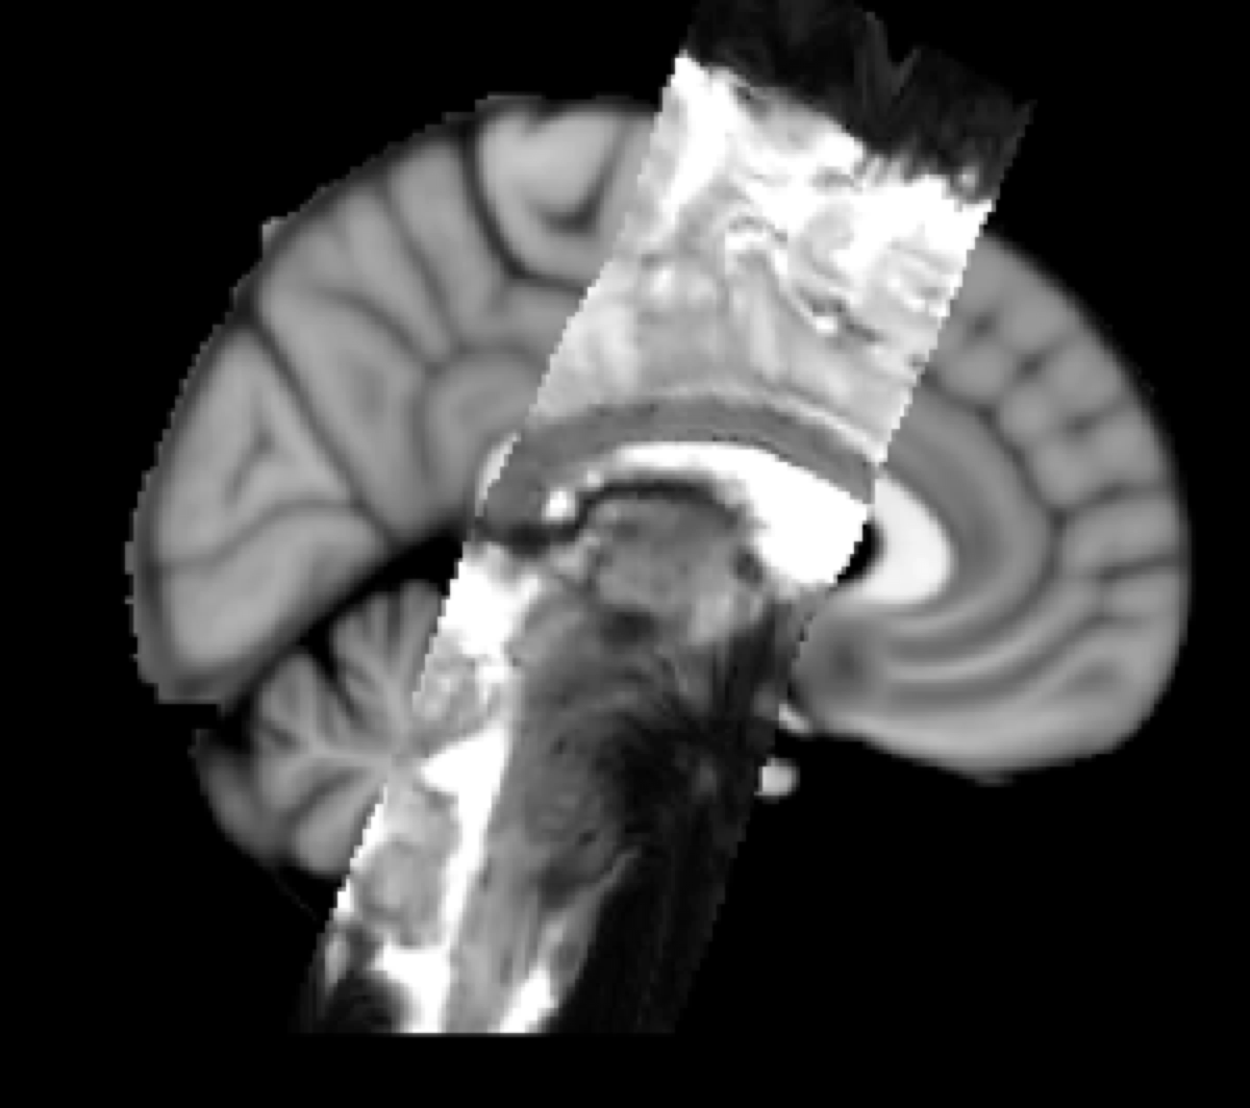

Example result: Two-stage registration

EPI (functional) to T1 Structural to Standard Space

- Step 1: boundary based registration (BBR) recommended from functional image to structural

- Command line tool is epi_reg (fieldmap distortion-correction can be included in this for stand-alone registrations)

- Step 2: Same as structural registration – FLIRT + FNIRT from structural to standard

- Check outputs: Check each step of the registration pathway separately as well as the total output, using FSLView to overlay the functional image resampled into structural space, and the structural image resampled into standard space